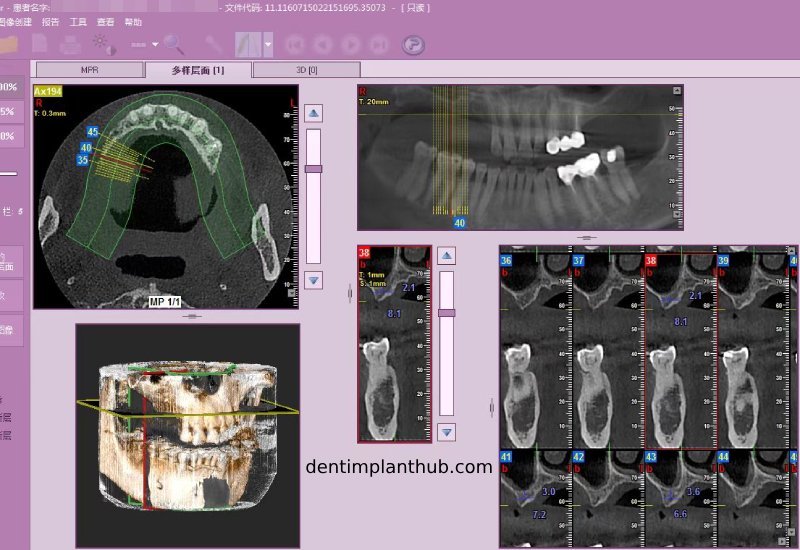

Screenshot of patient's CT on March 14, 2024